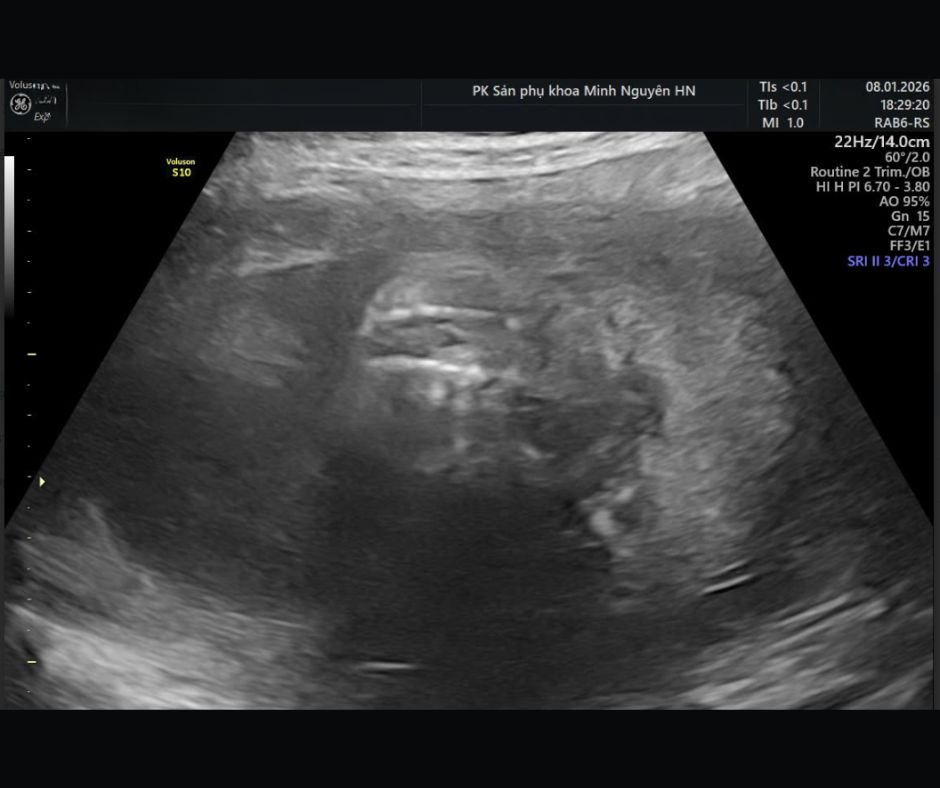

Chị H. mang thai 19 tuần, đến phòng khám Dr Tú y học bào thai với một tập hồ sơ khá dày. Trong đó có giấy siêu âm hình thái, phiếu xét nghiệm máu và usb chứa video siêu âm. Dòng kết luận khiến chị mất ngủ là nghi ngờ dị tật ống thần kinh, chẻ đôi đốt sống thể hở.

- Chẻ đôi đốt sống thể hở

Trong đó, chẻ đôi đốt sống thể hở là thể thường được phát hiện ở quý II.

Thứ hai là tư thế thai và góc khảo sát. Cột sống cần được nhìn đủ mặt cắt dọc, ngang và coronal.

Nếu mặt cắt cột sống chưa chuẩn, chỉ một đoạn cột sống mờ do tư thế thai hoặc góc tia lệch cũng có thể tạo cảm giác khuyết tật. Chẻ đôi đốt sống không thể kết luận từ một ảnh thiếu mặt cắt.

Nếu là chẻ đôi đốt sống thể hở, bác sĩ sẽ tập trung vào ba nhóm câu hỏi.

Tổn thương nằm ở đoạn nào của cột sống.

Có dấu hiệu kéo tụt hố sau và giãn não thất hay không.

Và dự kiến ảnh hưởng vận động, bàng quang–ruột ở mức nào.

Nếu tổn thương ở đoạn cao, nguy cơ ảnh hưởng vận động chi dưới thường lớn hơn. Nếu giãn não thất tiến triển, trẻ có thể cần đánh giá và can thiệp dẫn lưu dịch não tủy sau sinh. Nếu có bất thường kèm theo, cần mở rộng đánh giá di truyền và lập kế hoạch theo dõi sát hơn.